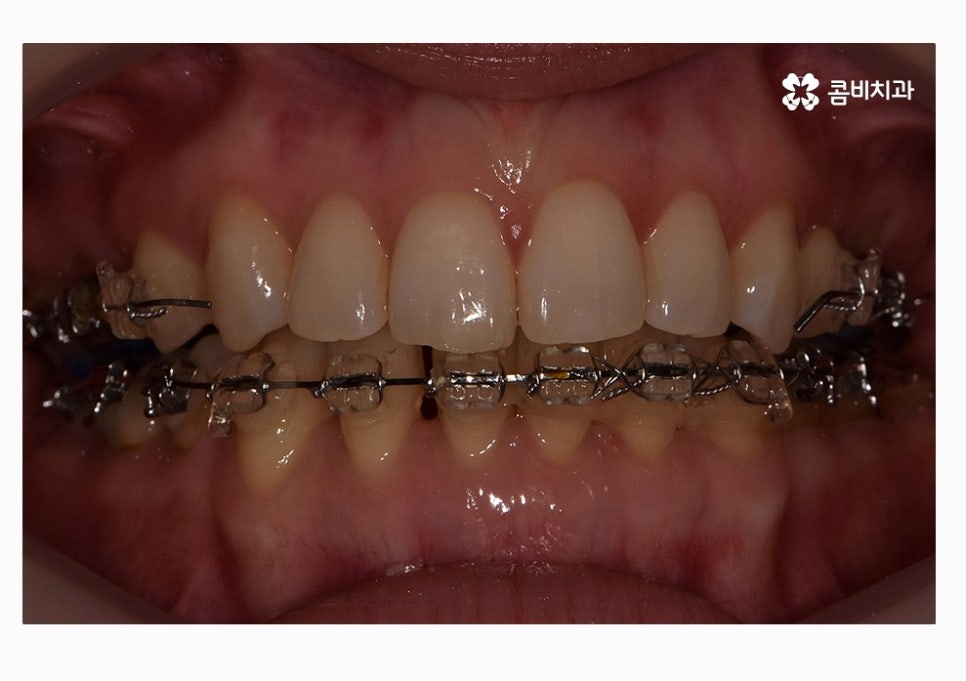

위 환자분의 경우에는 콤비교정의 치료 경과를 보면

아랫니가 정상교합이 되었고 치열도 보다 가지런하게

변화되고 있음을 알 수 있는데요.

콤비교정을 선택하시는 분들 중에서는 이처럼 치열과 함께

부정교합을 개선하고자 하시면서 직업적인 이유 등으로

교정 장치가 잘 보이지 않길 원하시는 분들에게 선호되고 있어요.

콤비교정의 또 하나의 장점은 윗니, 아랫니 모두

설측으로 치료를 진행하는 것에 비해 비용적인 절감이 가능하며

아랫니는 순측으로 교정이 진행되기 때문에 발음이

수월하고 이물감이 덜하다는 장점이 있는데요.

위 케이스는 총 1년 9개월 정도의 치료 기간이 소요되었으며,

개개인마다 치료 결과와 기간은 차이가 있을 수 있습니다.